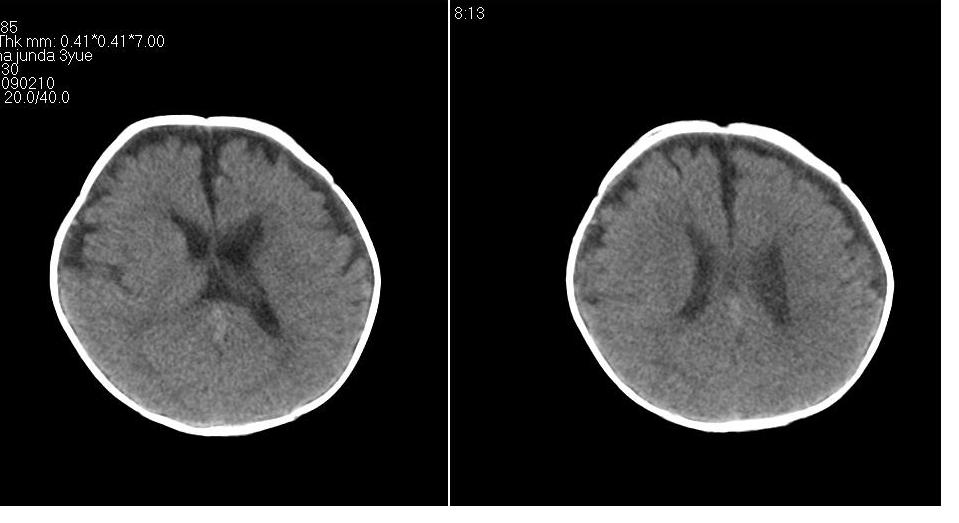

标题: PED1744:颅脑CT平扫

男 3个月,头大,颈软,头向后仰。

外部性脑积水

考虑外部性脑积水。

脑外间隙增宽,未见明显异常。

脑外间隙增宽,余未见明显异常。

脑外间隙增宽,现在好像有人说是一种发育性的交通性脑积水

蛛网膜增宽,外部性脑积水?

外部性脑积水(也就是诸位说的脑外间隙增宽);脑实质内未见异常密度灶,脑室系统无扩张,建议随访,毕竟临床症状听着怪吓人的。